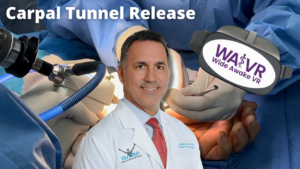

Hand Pain: Video Content

Engage with informative videos delving into the intricacies of hand discomfort, exploring its diverse causes and effective remedies. From expert interviews elucidating underlying conditions to step-by-step guides on therapeutic exercises, these videos offer valuable insights to empower you in managing and preventing hand pain.